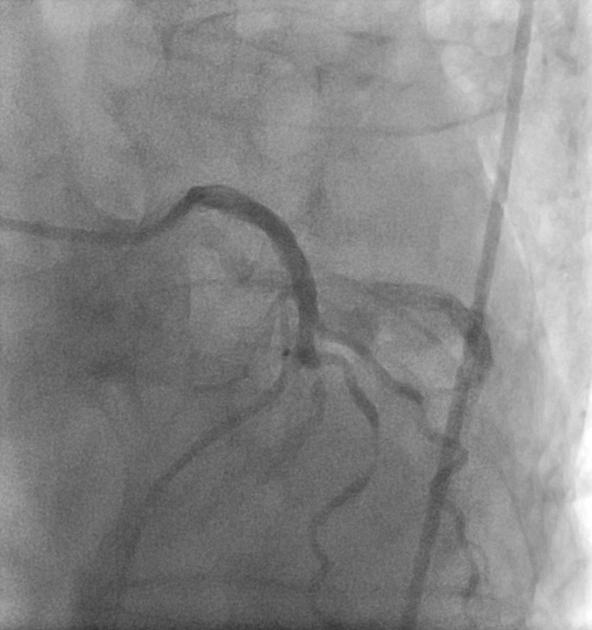

Puzzle 48

What's the Diagnosis?